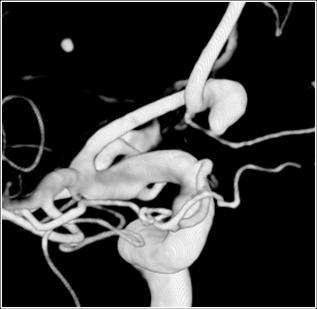

An aneurysm is an abnormal saccular or diffuse dilatation of an artery (Figure 1).

The modern treatment of aneurysms include surgical clipping, endovascular coiling, floater diversion, vessel sacrifice and observation of the aneurysm. (Figures 3, 4, and 5). The selection of therapy depends upon multiple factors including patient's age, disease state, medical conditions, aneurysm size and location.